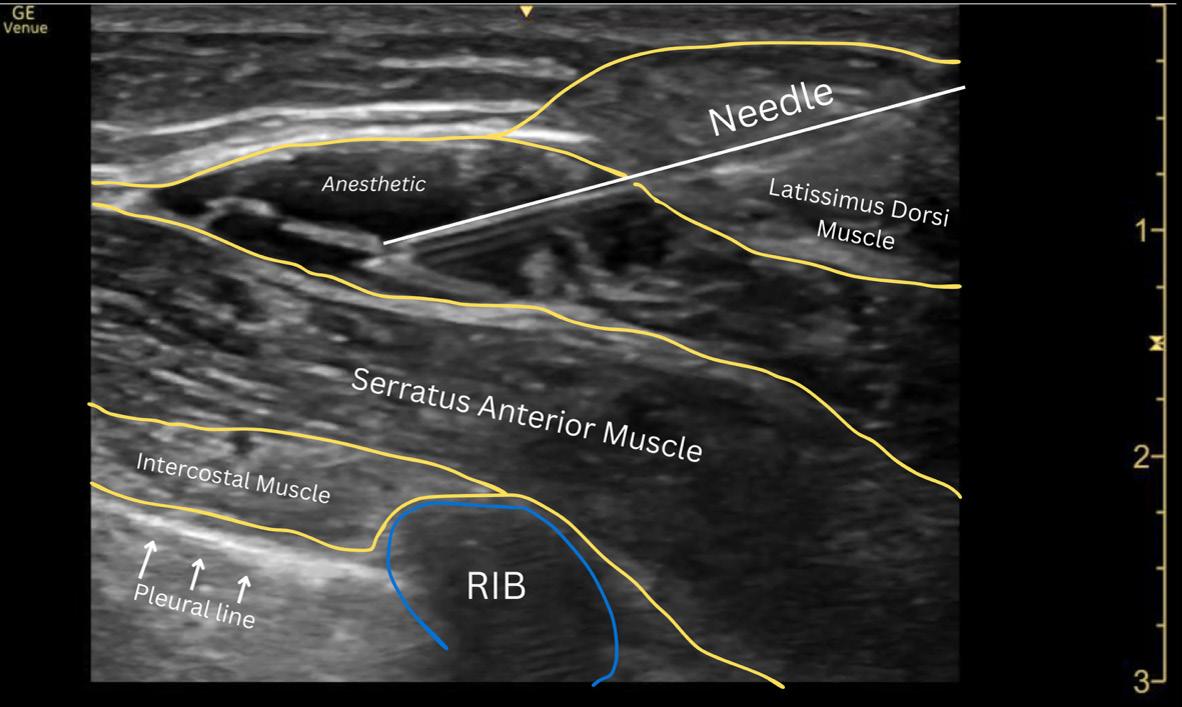

Dr. Artiga’s academic interests include ultrasound, education, and advocacy. Within SAEM RAMS, he has led initiatives such as the Ask-A-Chair educational podcast series, advocacy efforts related to unionization, social media campaigns to promote resident engagement, and the development of board review resources for emergency medicine certification. He has recently taught ultrasound to emergency medicine programs in Latin America.

It was an extremely humbling and eye-opening experience. I went to teach in my father’s country, El Salvador, where I had never visited before. I never truly understood the conditions he lived in beyond his words. All the issues that exist in the U.S. are magnified when you go to countries that don’t have similar resources. Medical decision making is limited by access to resources. It’s not about a lack of capability. I worked with incredibly brilliant doctors who just don’t have access to the same technology or infrastructure we have here. That’s why I believe in supporting ultrasound specifically in these settings. In capable hands, point-ofcare ultrasound can give a clinician life-saving information. Providing this tool and empowering physicians to use it can have a huge impact on individual patients and healthcare systems across the world.

For me, it’s been about chasing my passion and asking, “Who’s on this ride with me?” I’ve always been drawn to ultrasound. Through SAEM’s and the Academy for Emergency Ultrasound’s (AEUS’s) ultrasound didactics and activities, I’ve noticed similar faces showing up. These spaces allow for ideas to connect and develop in ways that don’t happen when you're working alone. You can’t have synergy in isolation. You need people who challenge and inspire you to promote growth. It’s individuals working together, learning from one another, and pushing ideas forward that produce progress.